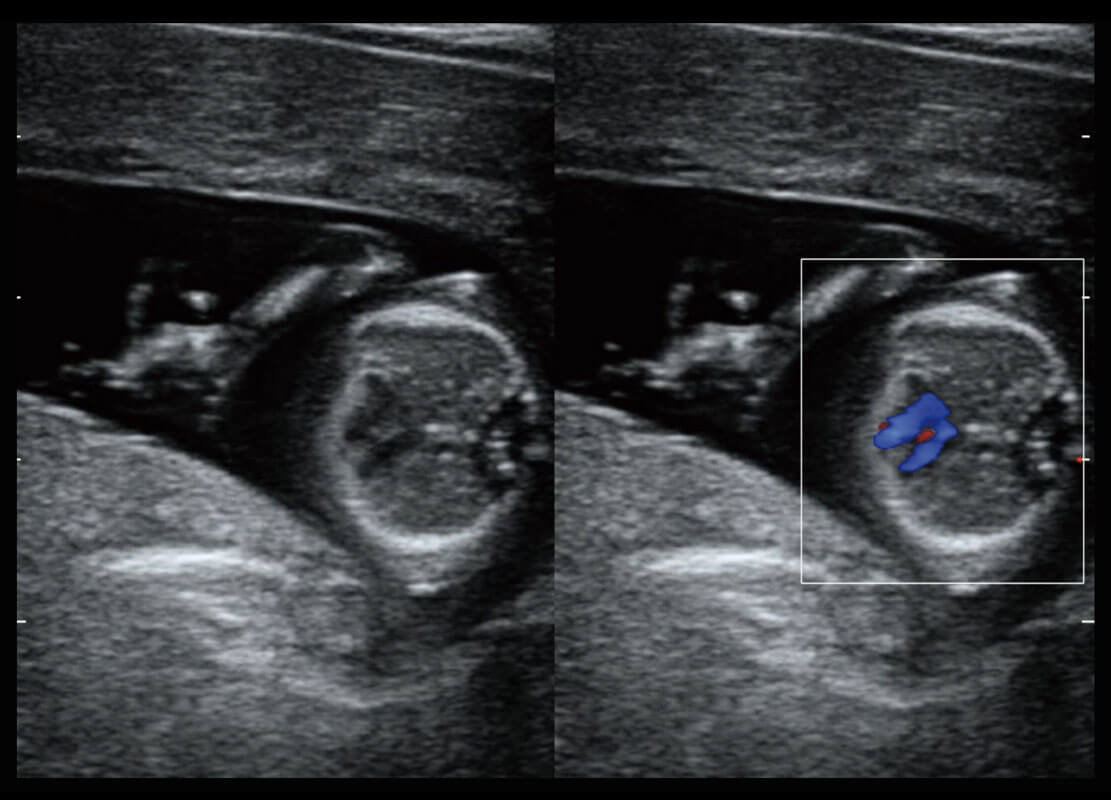

• 新生儿肝血管癌

• 新生儿脊髓圆锥

• 新生儿心脏

乳腺超声 / 新生儿

P60搭载宽频带线阵探头、宽景成像、弹性成像技术,为您提供乳腺应用方案。P60支持高频相控阵探头、线阵探头、腹部高频探头、腹部微凸探头等,丰富的探头群搭载敏感的彩色血流成像,适用于新生儿多种脏器检测要求,满足新生儿筛查需求。